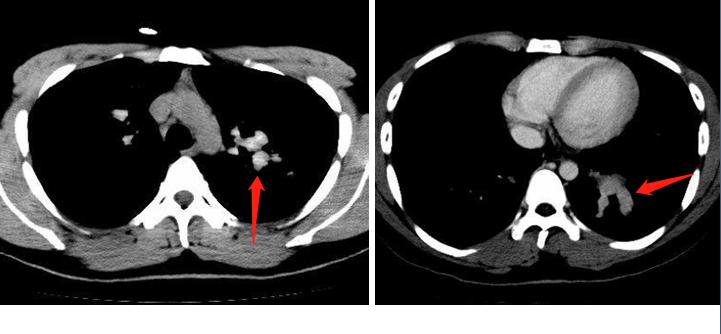

这种手指套样的改变,其实还可发生于肺结核、肺癌阻塞支气管等情况,为什么会直接考虑真菌感染呢?答案在下面这张图:

箭头区就是扩张的支气管,它有个典型特征是密度增高了,比血管的密度还高,提示里面有高密度的黏液栓,这是变应性支气管肺曲霉病(ABPA)的典型表现。

这种高密度黏液栓,是由于曲霉菌丝侵入小伙子气道后,引起变态反应,腺体分泌增加、炎细胞浸润,并且在菌丝作用下黏液变稠、浓缩,加上钙、金属粒子沉积形成(曲霉能富集空气中的铁、锰离子)。

见到这个高密度黏液栓,通常提示 局部炎症更严重,且容易复发。